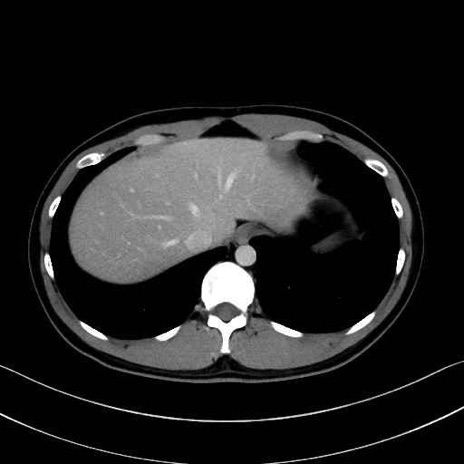

【症例】20歳代 男性 スクリーニング

■起始:典型的には腹腔動脈幹(celiac trunk)から左胃動脈・総肝動脈とともに三分岐し、脾動脈は左後上方へ向かう。

■走行:膵上縁または膵実質背側を蛇行しながら左方へ進み、膵尾部近傍で脾門へ至る。蛇行の程度は個体差が大きい。

■終枝:脾門部で複数の終末枝に分かれ、上極・下極枝や脾門枝群を形成する。胃短動脈群や左胃大網動脈はしばしば脾動脈から分岐する。